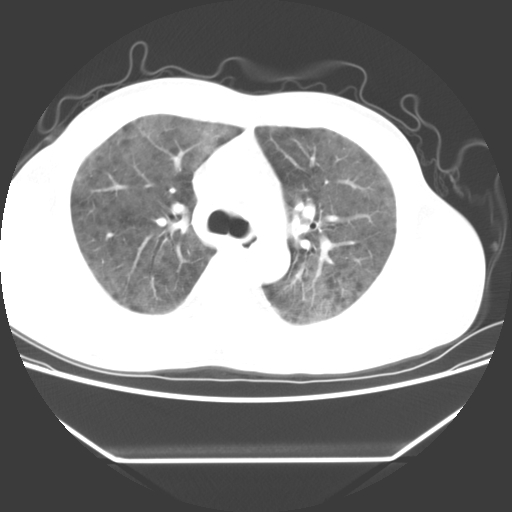

病人55岁,咳嗽,胸闷

忘了传病史了,病人55岁,咳嗽,胸闷

两肺部呈“毛玻璃”状改变,原因待查考虑感染性病变

病人是否发烧,两肺“磨玻璃”影,其间见空气支气管征和碎路石征。考虑肺泡蛋白沉着症。

两肺广泛对称磨玻璃样影,密度不均,考虑机遇性肺部感染。

双肺弥漫磨玻璃样病变,病史很重要。有感冒或发烧史,甲流不除外。无发烧可考虑肺泡蛋白沉积,但肺泡蛋白沉积边缘往往较清晰,与正常肺组织分界清晰

两肺弥漫间质性病变,考虑肺泡蛋白沉着症。建议进一步检查。

两肺“磨玻璃”影,其间见空气支气管征和碎路石征。考虑肺泡蛋白沉着症。